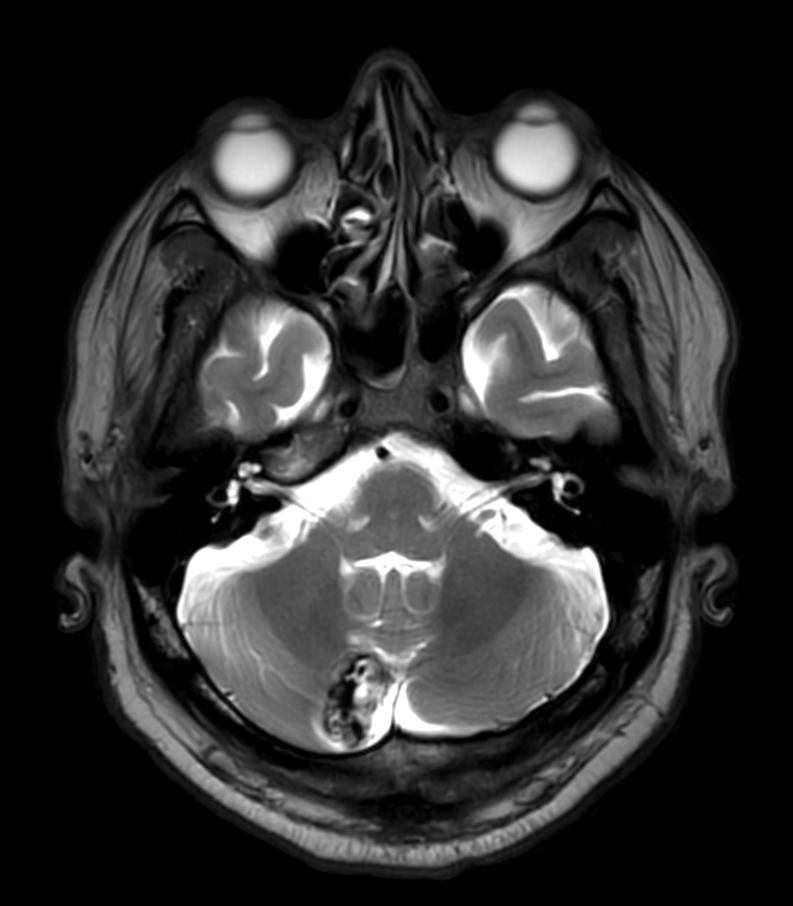

Patient with a lesion in the cerebellum. The ExamCard includes Compressed SENSE to accelerate the entire exam and techniques for motion reduced imaging (MultiVane XD), 3D imaging to acquire high resolution data in multiple directions, 3D susceptibility weighted imaging (SWIp), angiography sequences (Time-of-Flight and Contrast-Enhanced MRA with both arterial and venous phases), DTI with MultiBand SENSE to acquire a high number of diffusion directions in a short scan time and EPIC Brain to bring down any residual distortion.

T2w TSE MultiVane XD